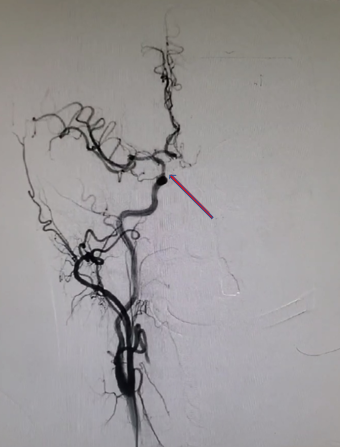

急诊DSA检查。

重要影像结论:左侧颈内动脉后交通段闭塞。

病变部位:左侧颈内后交通段-LC7。